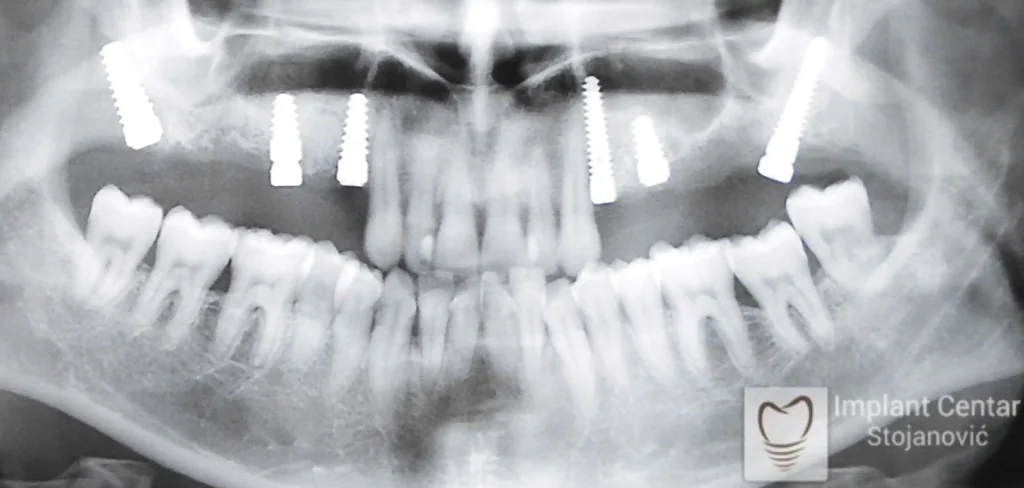

Na slici 1. i slici 2. prikazan je izgled pacijenta pre početka terapije – klinički i rendgenološki.

Nakon vađenja zuba, ugrađeni su implantati. Na slici 3 prikazan je ortopan snimak sa ugrđenim implantatima. Tokom perioda osteointegracije, pacijent je bio zbrinut fiksnim privremenim krunicama na implantatima, koje su izrađene samo dva dana nakon hirurške intervencije.